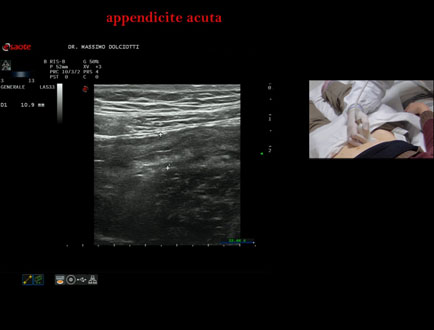

Data inserimento: 20/02/2026

Ecografia del: 13/02/2026

Strumento: Esaote MyLab Eight

Sonda: Lineare Multifrequenza 4-15 MHz

Età Paziente: M 22 anni

Motivazione dell'esame: da un giorno dolori addominali in sede ileo-cecale.

Commento all'esame: le immagini ed il video documentano, in sede ileo-cecale, appendice di spessore aumentato (9 - 10 mm - V.N. inferiore a 6 mm) con incremento della vascolarizzazione. Gli elementi ecografici segnalati orientano per appendicite acuta.

Conclusioni: appendicite acuta (acute appendicitis).

In collaborazione: Dr.ssa Marica Manfredi - Ancona, Dr. Ilir Qose - Ancona

Presentazione: Dr. Massimo Dolciotti - Ancona

Elaborazione digitale: Andrea Dini - Ancona